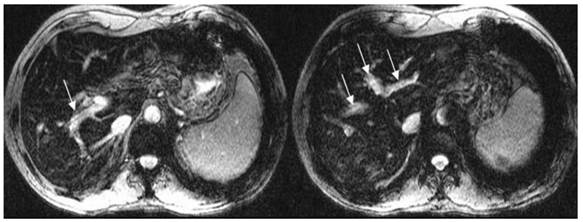

The comparison of PVT visualization score in T1WI, T2WI, T2*WI and CE-CT for two independent readers was illustrated in Table 1. The average score of PVT visualization in T2*WI was higher than T1WI and T2WI in location, size, boundary and conspicuity (t = 7.54 - 84.16, P<0.05), and higher than CE-CT in boundary and conspicuity (t = 3.03- 6.98, P<0.05) (Figure 1; Table 1).

Fig 1

T2*WI showing excellent PVT visualization. White thin arrows show the thrombosis; white thick arrows show the right portal vein.

Int J Med Sci Image